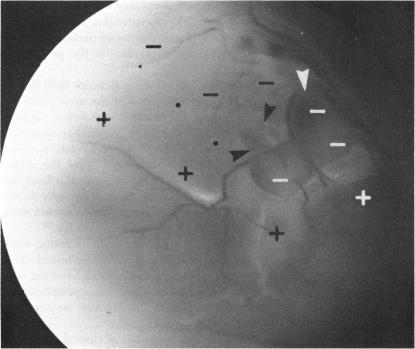

The following is a brief summary of the results in our ten groups of cases. The positive features of laser scotometry are emphasized. The normal response is well defined: there are no uncertain blind spot margins. The peripheral field is probably extended beyond 60 degrees nasally and superiorly. The size and shape of the small central scotomas associated with macular holes are easily defined and correlated directly with the visible edge of the hole. This result is distinct from the intact subjective response with cystoid maculopathy and surface wrinkling retinopathy. Plotting the margins of peripheral abnormalities such as retinal detachments, retinoschisis, and lattice degeneration is easily done. Schisis is distinguished by an absolute scotoma. This scotometry is facilitated by a larger "normal" field with the laser instrument. Lattice degeneration causes a field defect. A branch retinal artery occlusion shows a slightly jagged border, difficult to detect by standard methods. A cotton-wool spot does not show a total nerve-fiber-bundle defect. Small absolute scotomas are correlated with degenerative changes within nevi. Degenerative changes over small melanomas--ie, the orange spots--also produce absolute field defects. "Bear track" lesions have a normal field, whereas dense black isolated lesions are associated with absolute scotomas. In macular degeneration the bright laser test object is usually visible to the patient within detachments of neuroepithelium, detachments of the pigment epithelium, and over recent subretinal neovascularization. Response is absent over sharply-defined zones of pigment atrophy and over late subretinal fibrovascular mounds. In contrast to the degenerative cases, a selection of hereditary cases showed no direct correlation between the zone of pigment atrophy and the zone of absolute scotoma. The scotoma was much larger than the atrophic region, extending to the edge of the cream-colored subretinal spots. The laser target method sharply defines the absolute scotoma associated with papilledema. It also detects a slit-like nerve-fiber-bundle defect, suggesting progressive damage. Small, but possibly not the earliest, scotomas associated with glaucoma can be detected with laser scotometry. In some cases they are detected when the Goldmann perimetric field is normal. Late residual visual fields are easily defined, since fixation can be directly monitored. The vertical border of hemianopic defects can be defined within one degree of accuracy.

以下是我们十组病例结果的简要总结。重点强调了激光扫描视野检查的阳性特征。正常反应定义明确:盲点边缘不存在不确定性。周边视野在鼻侧和上方可能扩展超过60度。与黄斑裂孔相关的小中央暗点的大小和形状易于界定,且与裂孔的可见边缘直接相关。这一结果与黄斑囊样水肿和视网膜表面皱襞病变的完整主观反应不同。绘制周边异常(如视网膜脱离、视网膜劈裂和格子样变性)的边缘很容易。视网膜劈裂以绝对暗点为特征。使用激光仪器时,较大的“正常”视野有助于这种视野检查。格子样变性会导致视野缺损。视网膜分支动脉阻塞显示边界略呈锯齿状,用标准方法难以检测。棉絮斑不显示完全的神经纤维束缺损。小的绝对暗点与痣内的退行性改变相关。小黑色素瘤上的退行性改变——即橙色斑点——也会产生绝对视野缺损。“熊迹”病变视野正常,而密集的黑色孤立病变与绝对暗点相关。在黄斑变性中,明亮的激光测试物体在神经上皮脱离、色素上皮脱离以及近期的视网膜下新生血管形成区域通常对患者可见。在色素萎缩的清晰界定区域和晚期视网膜下纤维血管隆起上方无反应。与退行性病例不同,一些遗传性病例显示色素萎缩区域与绝对暗点区域之间无直接相关性。暗点比萎缩区域大得多,延伸至淡黄色视网膜下斑点的边缘。激光靶点法能清晰界定与视乳头水肿相关的绝对暗点。它还能检测到一条狭缝样的神经纤维束缺损,提示进行性损害。激光扫描视野检查可检测到与青光眼相关的小暗点,但可能不是最早出现的。在某些情况下,当戈德曼视野计检查视野正常时就能检测到它们。晚期残余视野很容易界定,因为可以直接监测注视情况。偏盲缺损的垂直边界可以精确到一度以内界定。